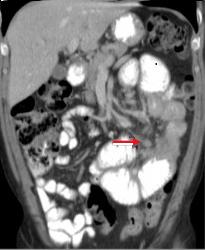

Mema cas ( fleche

rouge ) en coupe cornale ( frontal )

| Adenocarcinoma du duodenum a

extension locale vers le pancreas ( fleche rouge ) .

Dilatation du duodenum en amont |